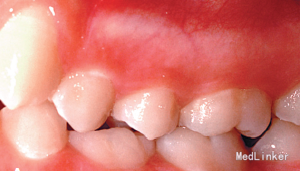

15岁女孩,牙列不齐

左下第二乳磨牙滞留,上下牙列轻度拥挤不齐.全景示左下第二乳磨牙无相应的恒牙,先天缺失35牙